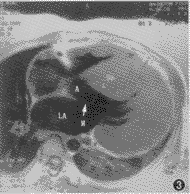

图3 非匀称型肥厚型心肌病。横轴面T1WI, 示室间隔及左心室前、侧壁显著肥厚,左心室腔缩小,室间隔左心室面与二尖瓣前叶(箭头)构成狭窄的流出道。LA为左心房,A为主动脉,SP为室间隔

肥厚型心肌病心肌肥厚主要累及左心室前侧壁 (图3)和室间隔,肥厚显著者常常伴有心室流出道的梗阻,心室后壁不易受累。与正常心肌相比,肥厚心肌增厚率下降(图4,5);心腔容积不同程度减少,以舒张末期为主;左心室泵血功能下降,表现为心肌收缩时限延长,每搏输出量下降,其程度似与心肌肥厚程度呈正比,但射血分数并未下降(表1)。

伴有血流动力学梗阻者见于非匀称型心肌病,表现为左心室流出道狭窄,舒张末期平均前后径为(1.3±0.4) cm[非梗阻型为(2.0±0.1) cm]。长轴四腔面cine-MRI示左心室收缩时,室间隔肥厚,心肌凸向左心室面,二尖瓣前叶向前移,使流出道进一步狭窄,并可见由于高速射血引起血流信号丢失而出现的“涡流”征。